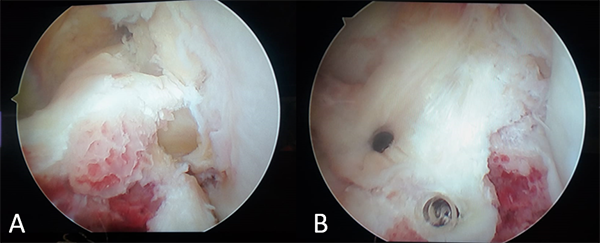

Se realizaron los portales habituales de rodilla: anteromedial y anterolateral, se evidenció lesión en asa de balde del menisco interno, luxada hacia intercóndilo asociada a fractura grado 3 de espina tibial (fig. 4).

Figura 4: Visión artroscópica de rodilla derecha. Fractura de espina tibial y asa de balde del menisco interno.

Se realizó la reducción del asa y luego se efectuó la sutura meniscal interna con tres Meniscal Cinch® (Arthrex, Naples, FL, EE. UU.) en tercio posterior y dos puntos fuera-dentro, verticales con FiberWire 2.0® (Arthrex, Naples, FL, EE. UU.) logrando una reducción y estabilidad satisfactorias (fig. 5).

Figura 5: Fijación de la lesión meniscal con cinco puntos, tres sistemas todo-adentro Meniscal Cinch® y dos puntos fuera-dentro.